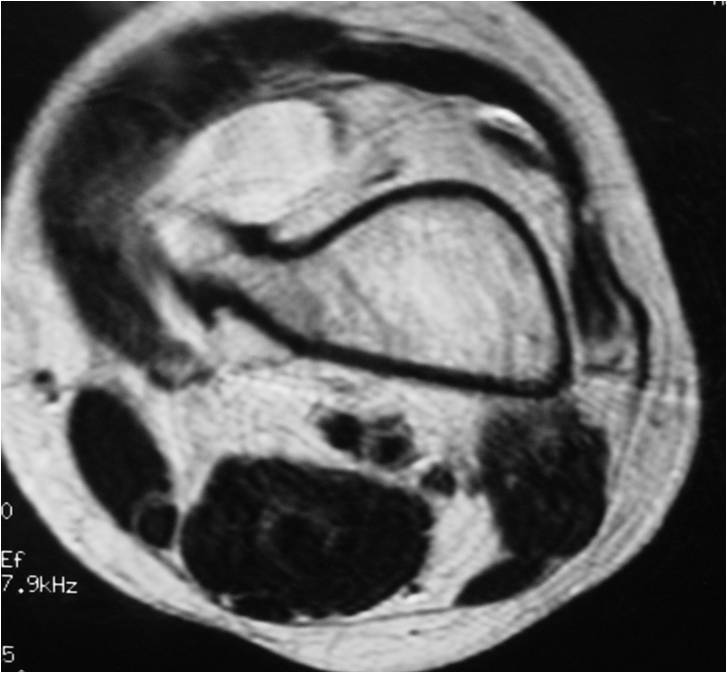

- Best test for evaluating thickness of cap and surrounding bursa

- Intermediate T1W Images

- High Intensity T2W Images because of fluid content

MRI: Secondary Chondrosarcoma of Proximal Femur: Thick Cartilage Cap (>2cm)